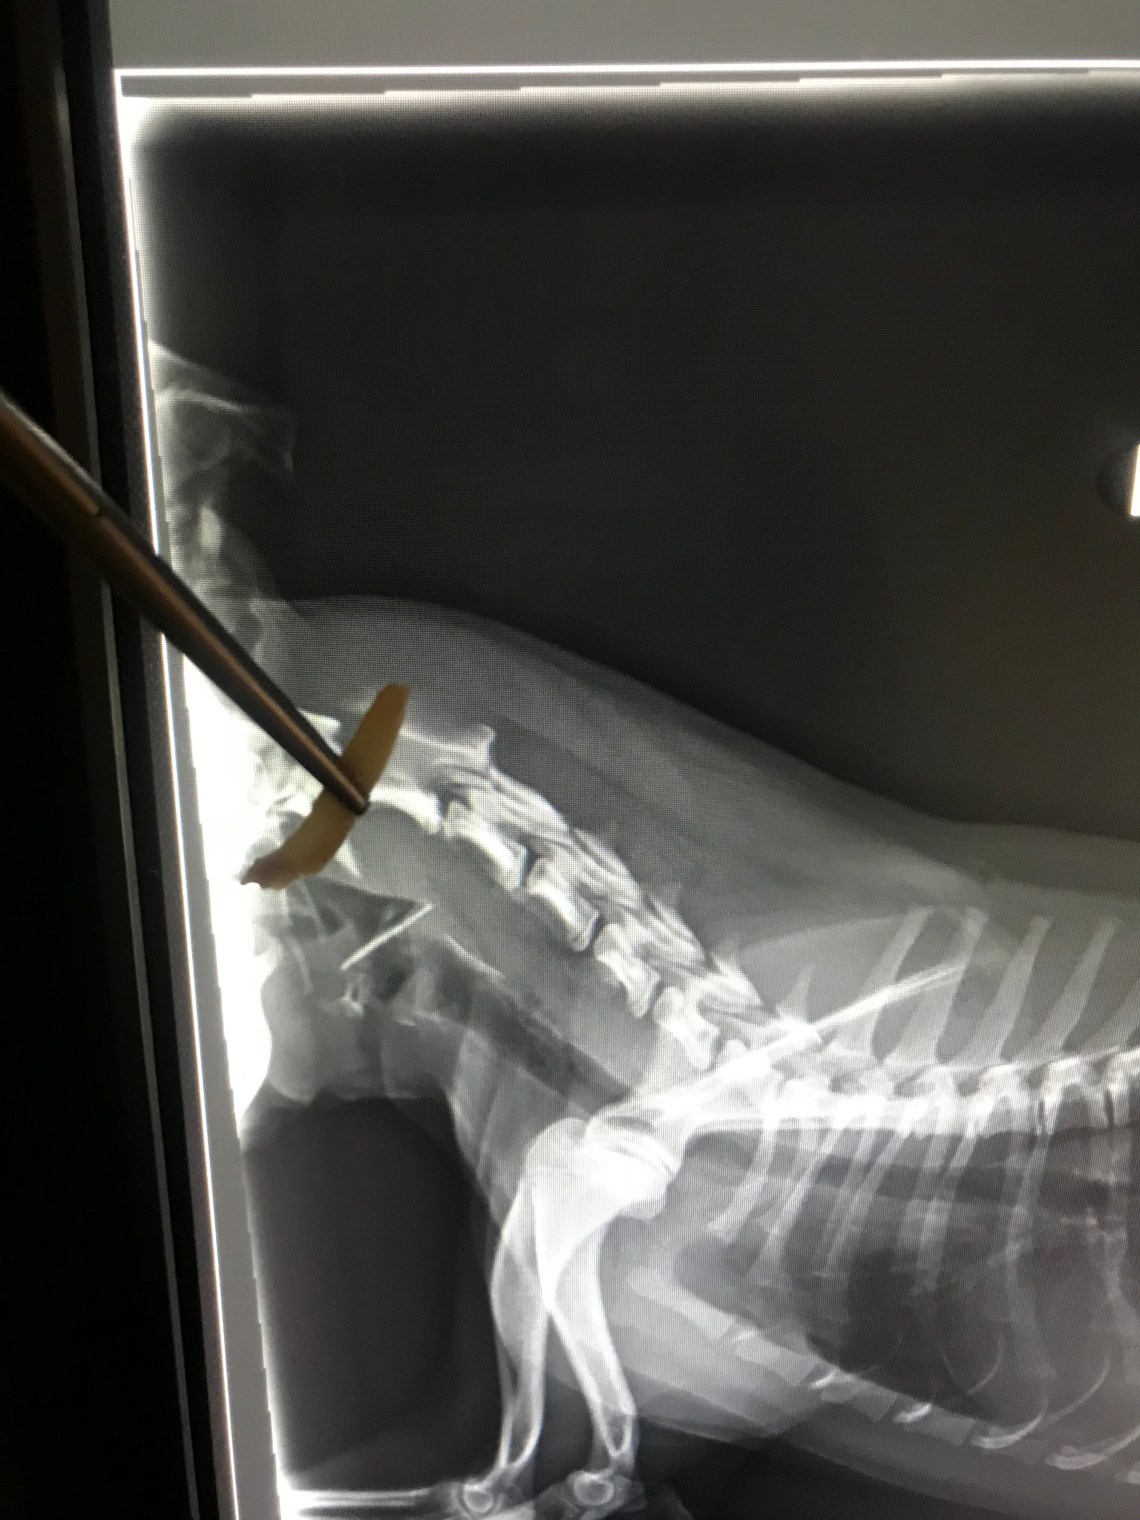

Here is a photo of a radiograph that includes the shard of chicken bone that was lodged in this dog’s throat.

He got into the garbage can and ate chicken wings.

This dog had to be fully sedated and the bone was able to be removed with a pair of forceps.